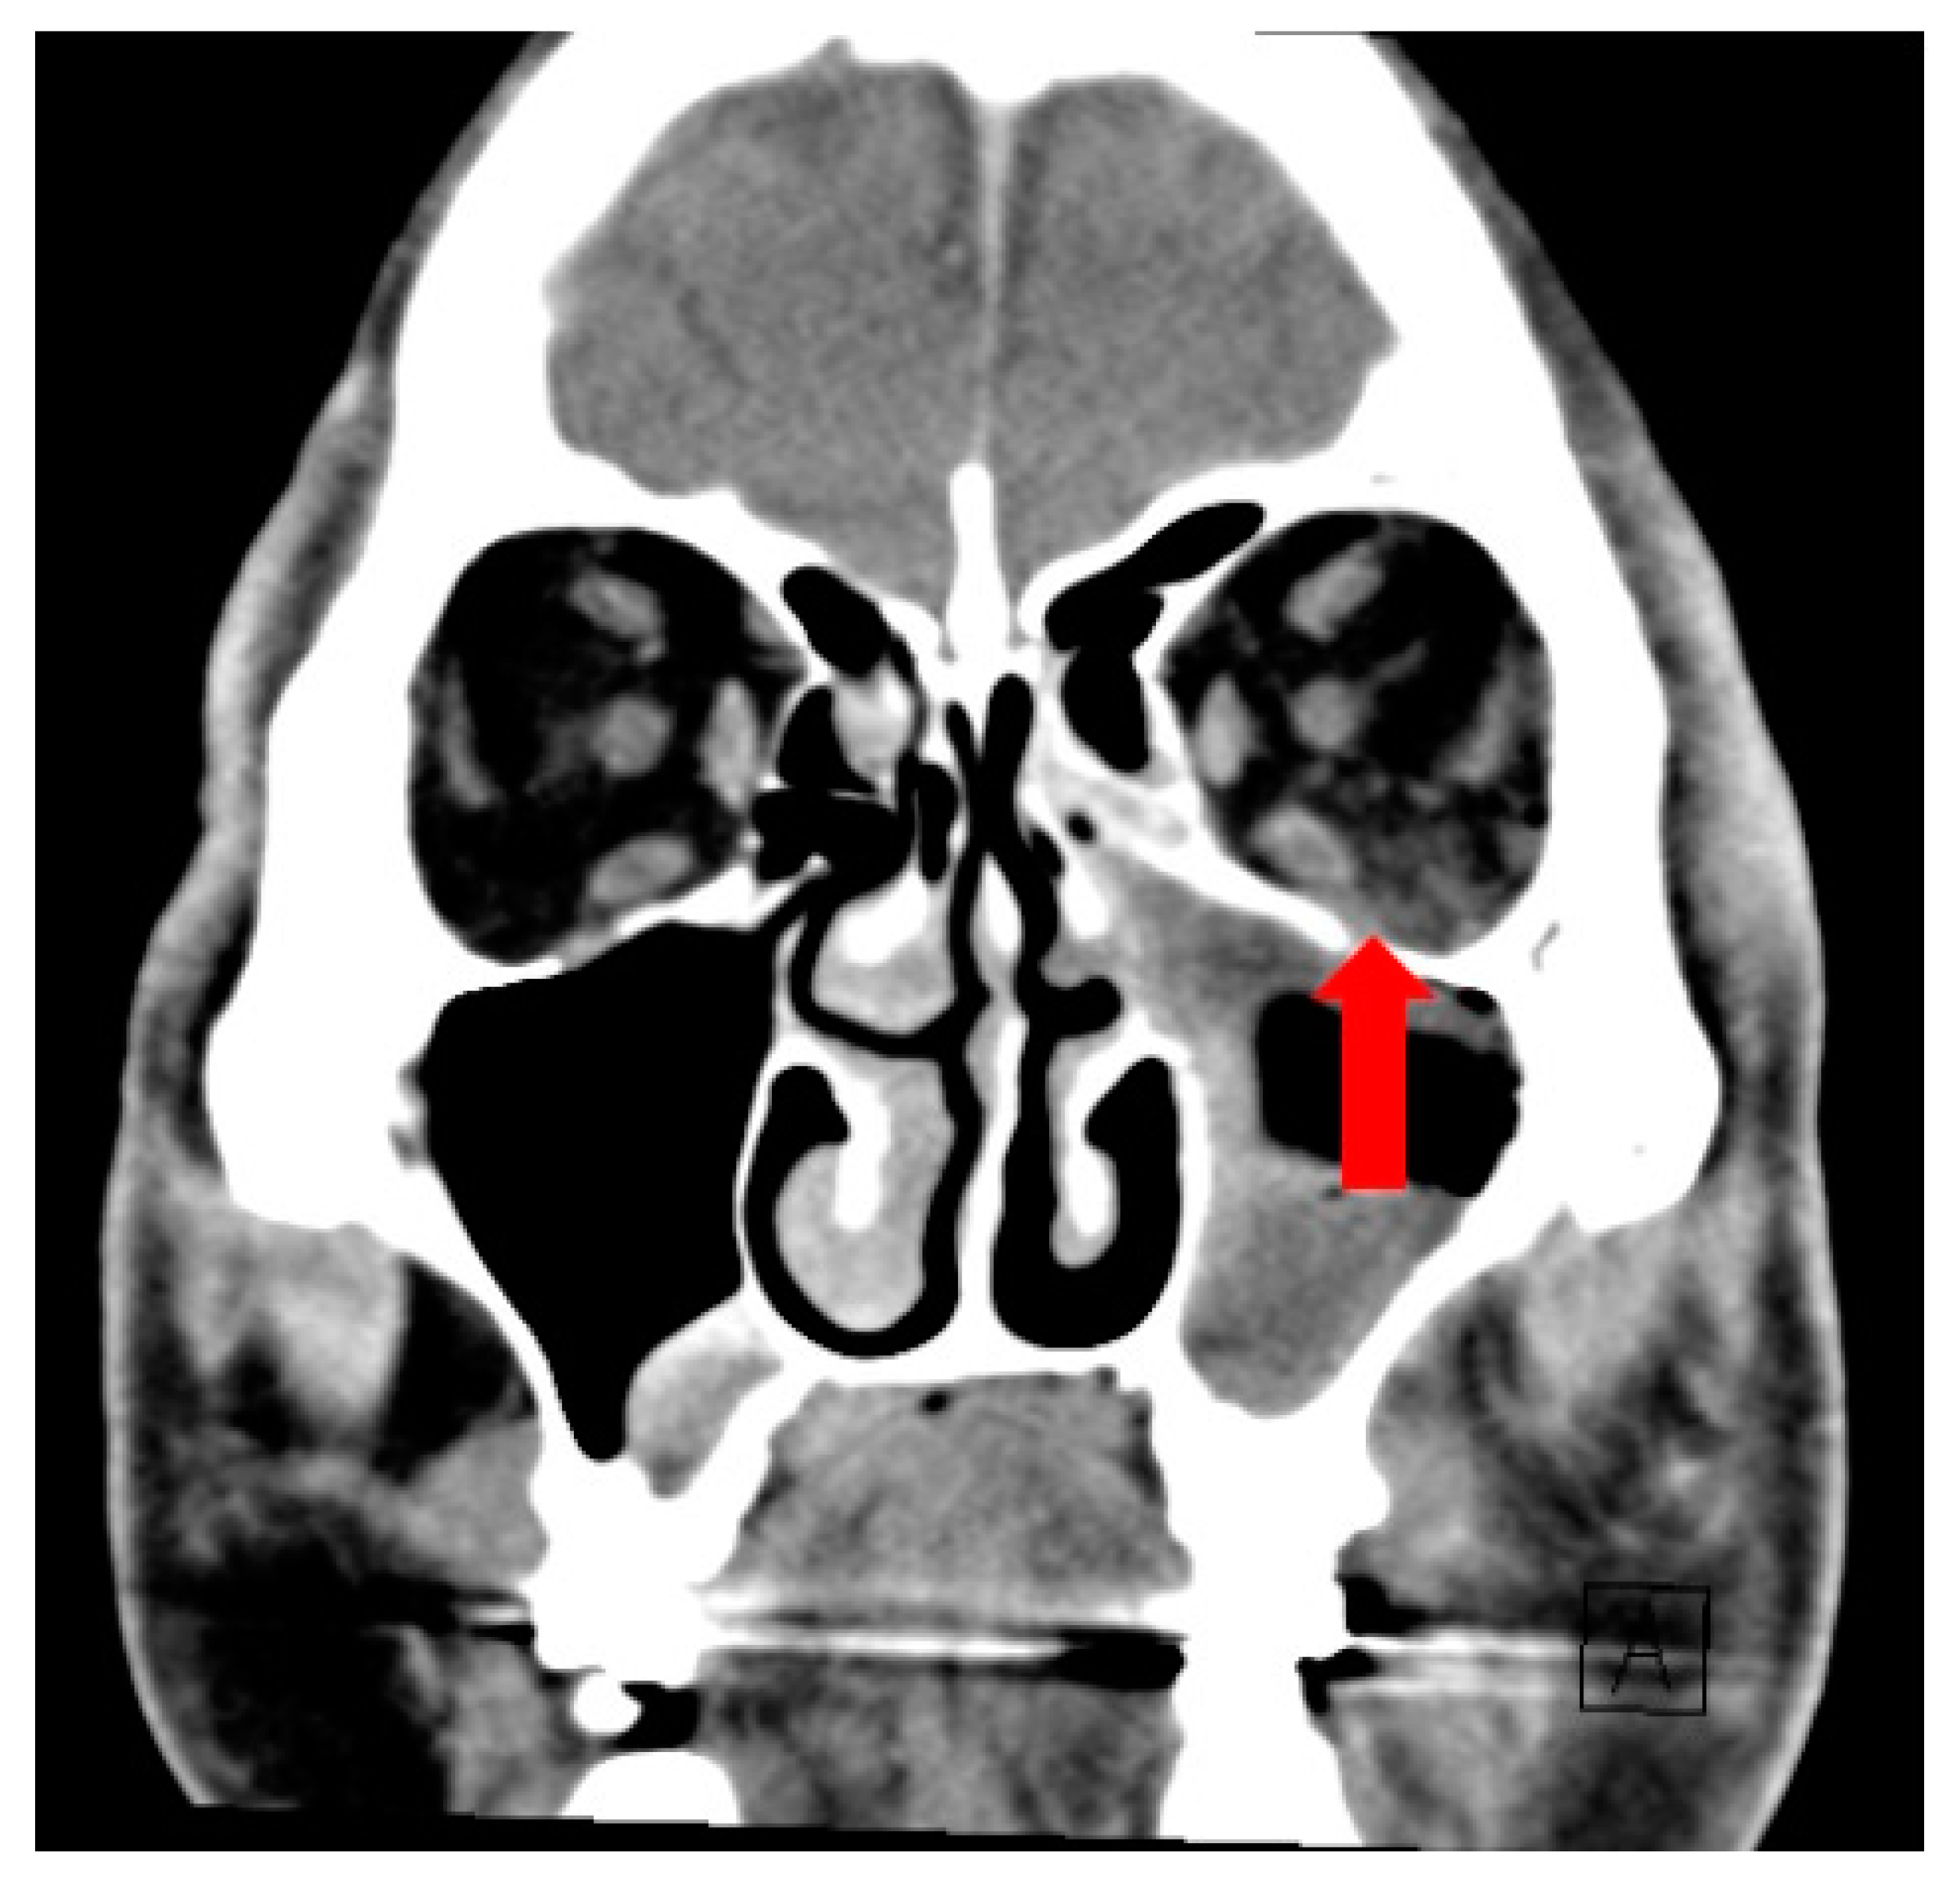

Figure 2.

Coronal CT image showing fat stranding in the left extra-conal orbital fat (red arrow).